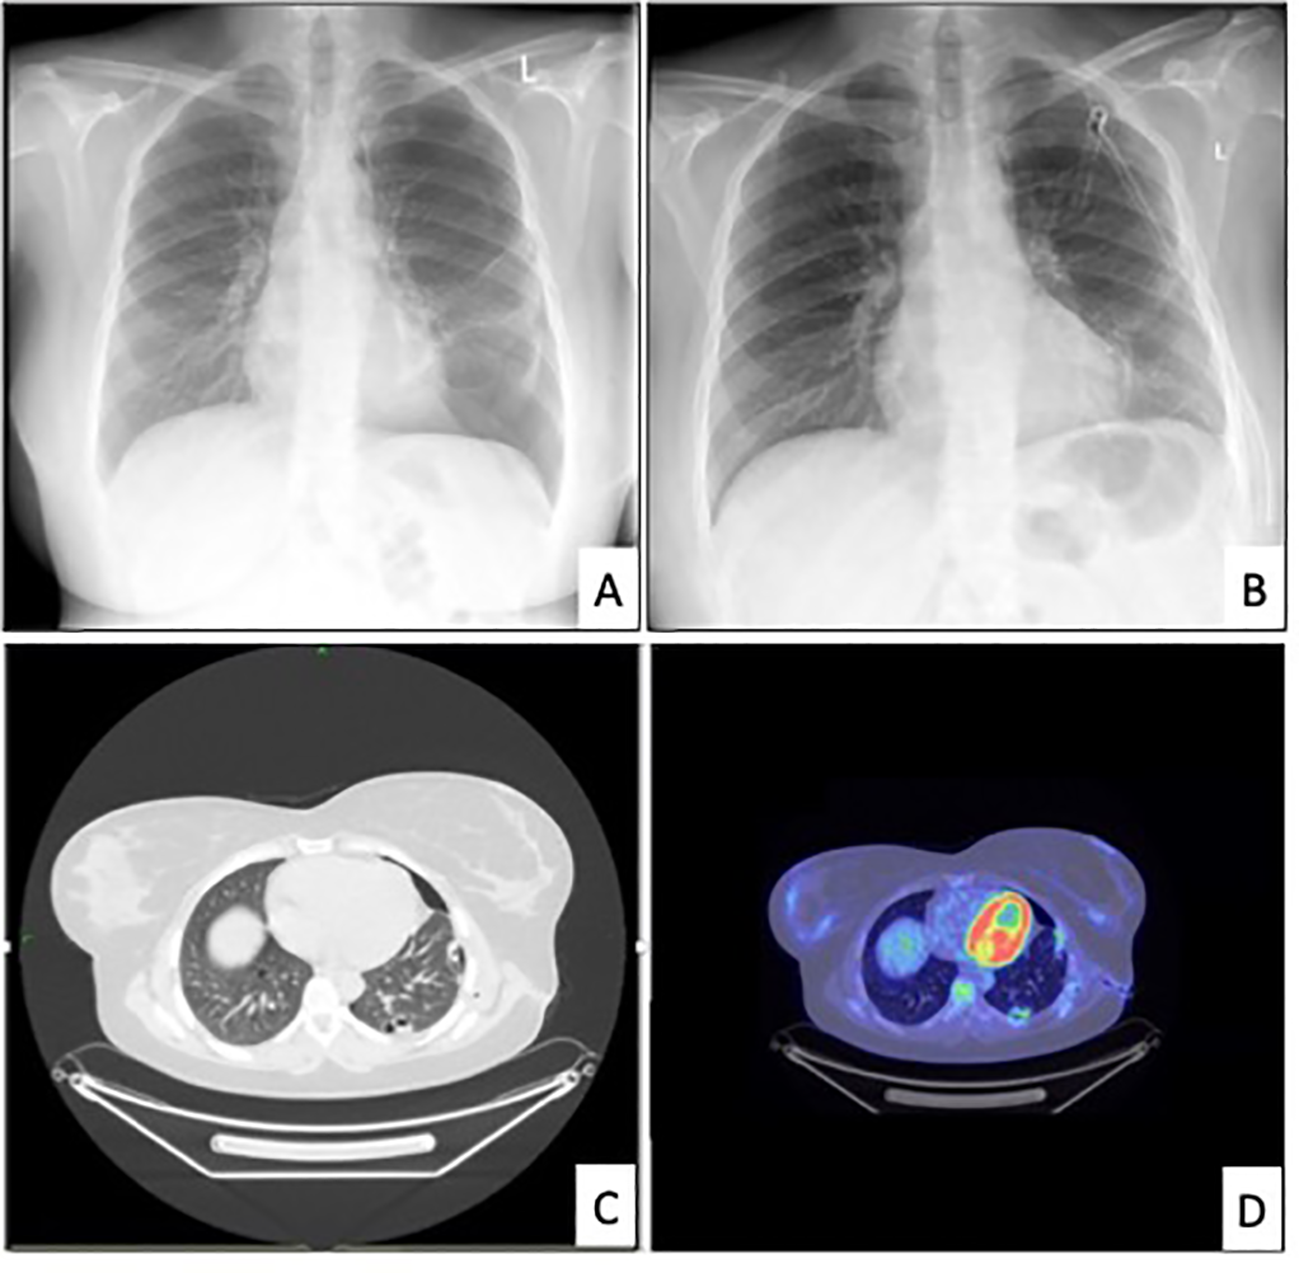

The patient underwent a standard radiological workup and oncological staging due to possible malignancy, with a subsequent PET-CT performed. In the left lung, a 2.2-1.4 cm lesion was found, surrounded by multiple subpleural bullae at the margin of segments 9-10. The scan indicated a slight accumulation of FDG with an SUV-max of 4.2. (Figure 1) An additional hilar lymph node was found with an SUV-max of 4.9, measuring 1 cm in size. There was residual postoperative activity with an SUV-max of 3.3 in the atelectatic region in the left lower lobe around the thoracic drain. FDG avidity in the right ovary (SUV-max of 10.8) was attributed to the menstrual cycle. (The later regular gynecological follow-up showed no progression in size or other characteristics regarding the ovaries.) Otherwise, the abdominal cavity and other parts of the body were negative on the PET scan.

Figure 1

Relevant radiological images. [(A) chest x-ray revealing the recurrence of pneumothorax in June 2022. (B) chest x-ray after drainage, (C) chest CT in June 2022, (D) PET-CT in July 2022].